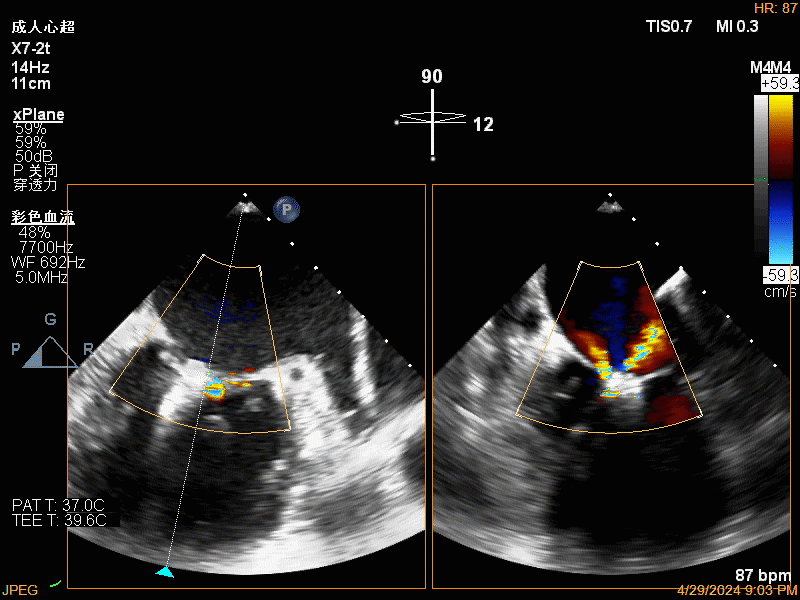

团队在反流最严重的2区精准植入1枚二尖瓣夹,即刻反流下降至微量,血压即刻上升20mmHg,跨瓣压差不升反降,由3mmHg降至2mmHg,改善效果明显,手术仅耗时一个半小时。 这是时隔四年继2020年指导开展区域内首例TAVR(经导管主动脉瓣置换)手术之后,陈茂教授再次带领华西团队,指导开展内自同城区域首例TEER术。陈茂教授对四院心内科心超图像的采集、房间隔穿刺的技巧、手术流程细节的把握、团队的默契配合、术前术后的管理表示称赞,鼓励四院心内科再接再厉造福区域患者。 患者为71岁老年女性,反复出现心累、气促已经超过10年,10多年来心衰的症状逐渐加重,间隔时间越来越短,且近1个月来已经3次因心衰住院,本次住院前已经无法耐受缓慢步行、如厕等日常生活,BNP超过了3000ng/ml。心电图为房颤,心超示左心室明显增大(65mm),重度二尖瓣反流(4+,CarpentierI+IIIb型),射血分数仅为31%。前叶长度:2.27cm且瓣尖增厚,后叶长度:1.14cm且局部钙化,瓣口面积:4.08cm2,反流宽度:1.7cm。患者及家属均拒绝外科开胸手术。 难点: 1.食道超声下该患者房间隔较厚较韧,且粗测高度仅为4.0cm,对穿刺的位置和技巧有较高要求; 2.左心扩大,反流宽度约17mm,放一个夹子可能不能有效解决反流,如放两个夹子需side by side 平行放置,但放置两个夹子有术后狭窄的风险; 3.前后叶对合似有间隙,若选用长宽夹子,会增加瓣叶张力,有瓣叶撕裂的风险,若选用短宽夹子,其捕获瓣叶的难度将增加; 4.患者心功能极差,手术需稳、准、快,不能耐受任何并发症风险。 影像资料 房间隔穿刺

![]() Trajectory 瓣下抓捕

![]() 瓣下抓捕